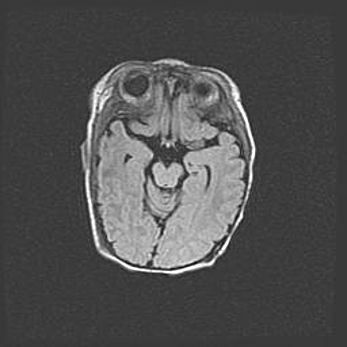

Церебральная ишемия II.

Возраст: 5 дней

Вес: 3400 г

Пол: женский

Окружность головы: 35 см

Срок гестации: 39 недель

Церебральная ишемия – это заболевание, характеризующееся недостаточностью (гипоксией) либо полным прекращением (аноксией) снабжения мозга кислородом по причине закупорки одного или нескольких сосудов. Это приводит к  что метаболическим расстройствам различной степени тяжести в тканях головного мозга, развитию коагуляционных некрозов и гибели нейронов.